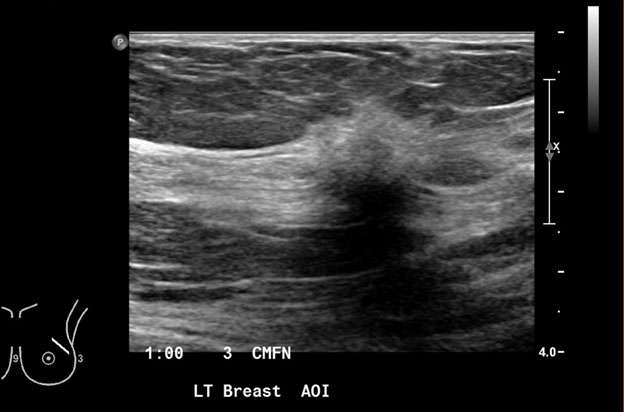

3. Irregular: the shape of the mass is neither round nor oval (Figure 3).

Mammography: Masses Figure 3

Figure 3: A) Mammography of the left breast with MLO view demonstrates irregular, spiculated mass in the left breast at 12 o'clock (big white circle). Additional calcifications in the left breast at 8 o'clock at anterior depth located 2 centimeters from the nipple, three additional groups of calcifications in the central and lower inner left breast are also suspicious (small white circles). B) Ultrasound of the left breast represents an irregular, spiculated hypoechoic mass, BI-RADS Category: 4C suspicious finding. Ultrasound guided biopsy was recommended and confirmed invasive ductal carcinoma, grade 2.